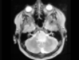

74.患者,男,50岁。发热,头痛,结合影像图像,最可能的诊断是 ( )